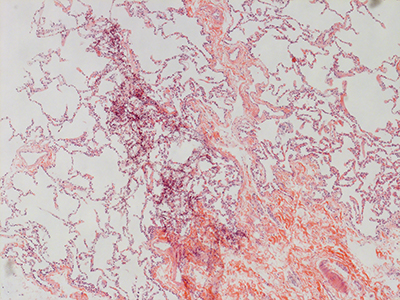

31 Year Old Adult Human Lung DD034L H&E

31 Year Old Adult Human Lung D0036 H&E

31 Year Old Adult Human Lung DD037 H&E

31 Year Old Adult Human Lung D003 H&E